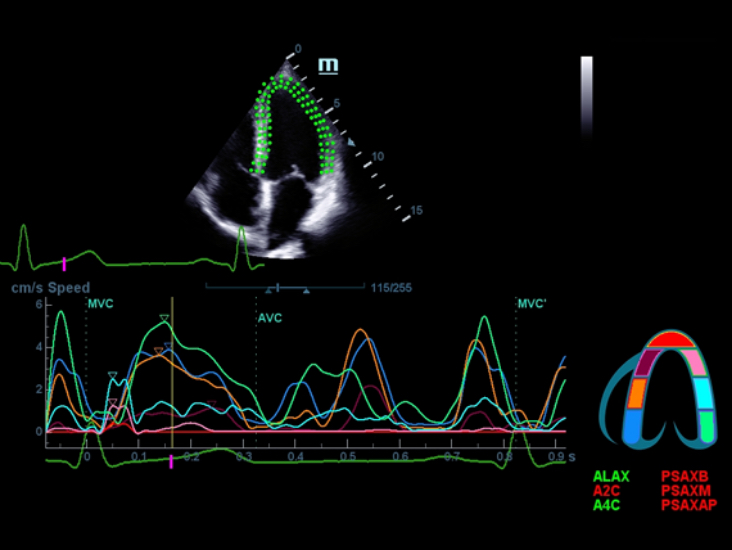

Sobre la base de un profundo conocimiento de las necesidades del cliente, el DC-60?ECHO con X-Insight estå dise?ado para brindar alta eficiencia con imågenes precisas, lo que se ve potenciado con eXpress Clarity (claridad exprés), eXceptional Intelligence (inteligencia excepcional) y eXceeding Experience (experiencia extraordinaria).

eXceeding Experience

Experiencia con alta productividad